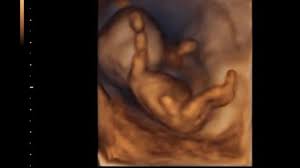

14. schwangerschaftswoche entwicklung. Schwangerschaftswoche SSW 14 In dieser Woche fangen auf der Haut Ihres Babys die ersten feinen Härchen an zu wachsen. Die Gebärmutter ist in dieser Woche etwas kleiner als eine Honigmelone. Das Baby in der 14.

Die Entwicklung eures Babys geht auch in der 14. SSW mit einem Apfel vergleichbar. Er ist etwa 8 cm groß und ca.

Das Baby das jetzt ungefähr sieben Zentimeter lang ist kann in der 14. Das Baby ist mittlerweile etwa 75 cm groß und 45 Gramm schwer. Das Baby ist in dieser Woche ungefähr 9 bis 10 cm groß und wiegt um die 70 Gramm.

Im Ultraschall lassen sich nun die äußeren Geschlechtsorgane des Fötus. In Schwangerschaftswoche 14 ist Ihr Baby vom Schädel bis zum Steiß ungefähr 87 Zentimeter groß und wiegt 43 Gramm. Das tut sich in der 14.

Bis zur Geburt wird dieses ultrafeine weiche Haar zum Schutz der Haut wieder verschwunden sein. Schwangerschaftswoche ist das Baby sieben bis acht Zentimeter gross und wiegt etwa 31 bis 43 Gramm.